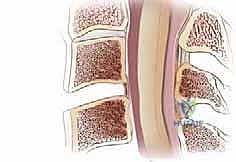

3. النتوءات العظمية (Osteophytes/Bone Spurs)

كرد فعل طبيعي لاحتكاك العظام الناتج عن تآكل الغضاريف، يقوم الجسم بتكوين زوائد عظمية لمحاولة تثبيت المفصل. للأسف، تنمو هذه الزوائد غالباً داخل القناة الشوكية أو في مسار الأعصاب، مما يسبب ألماً شديداً.